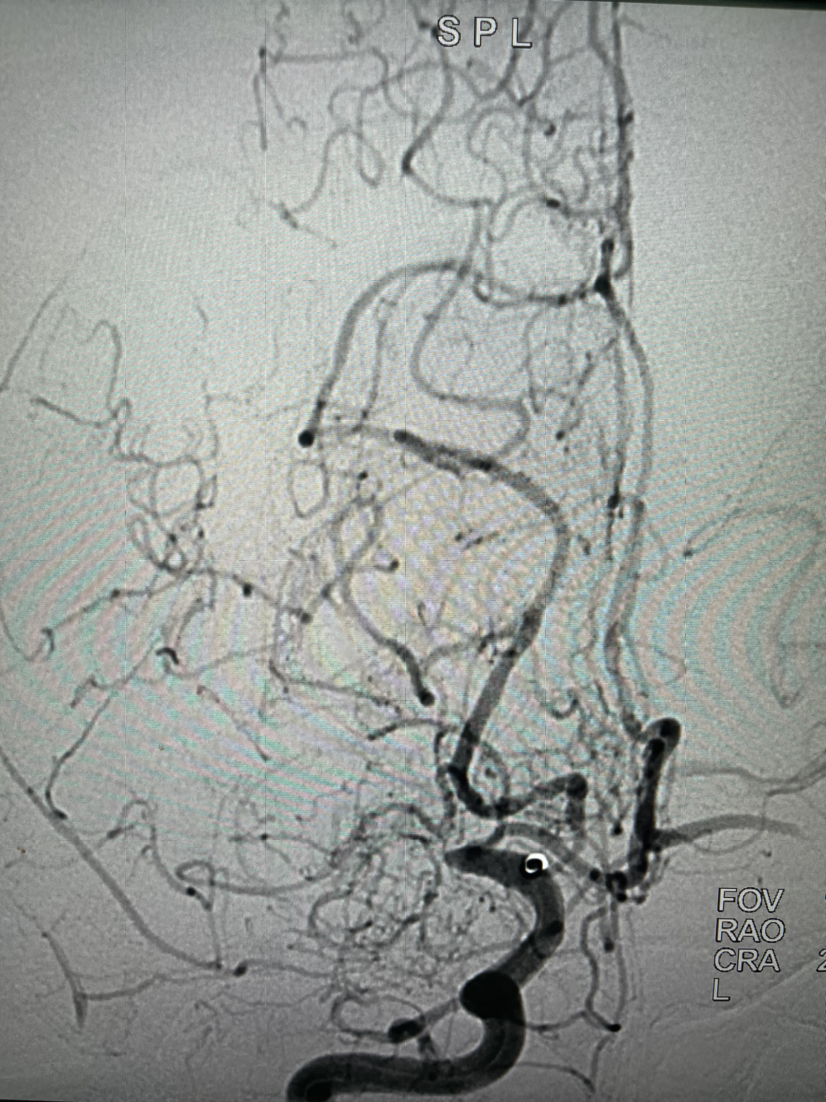

右侧颈内动脉造影提示大脑中动脉起始以远闭塞

6F115c m中间导管到位后右侧工作位造影